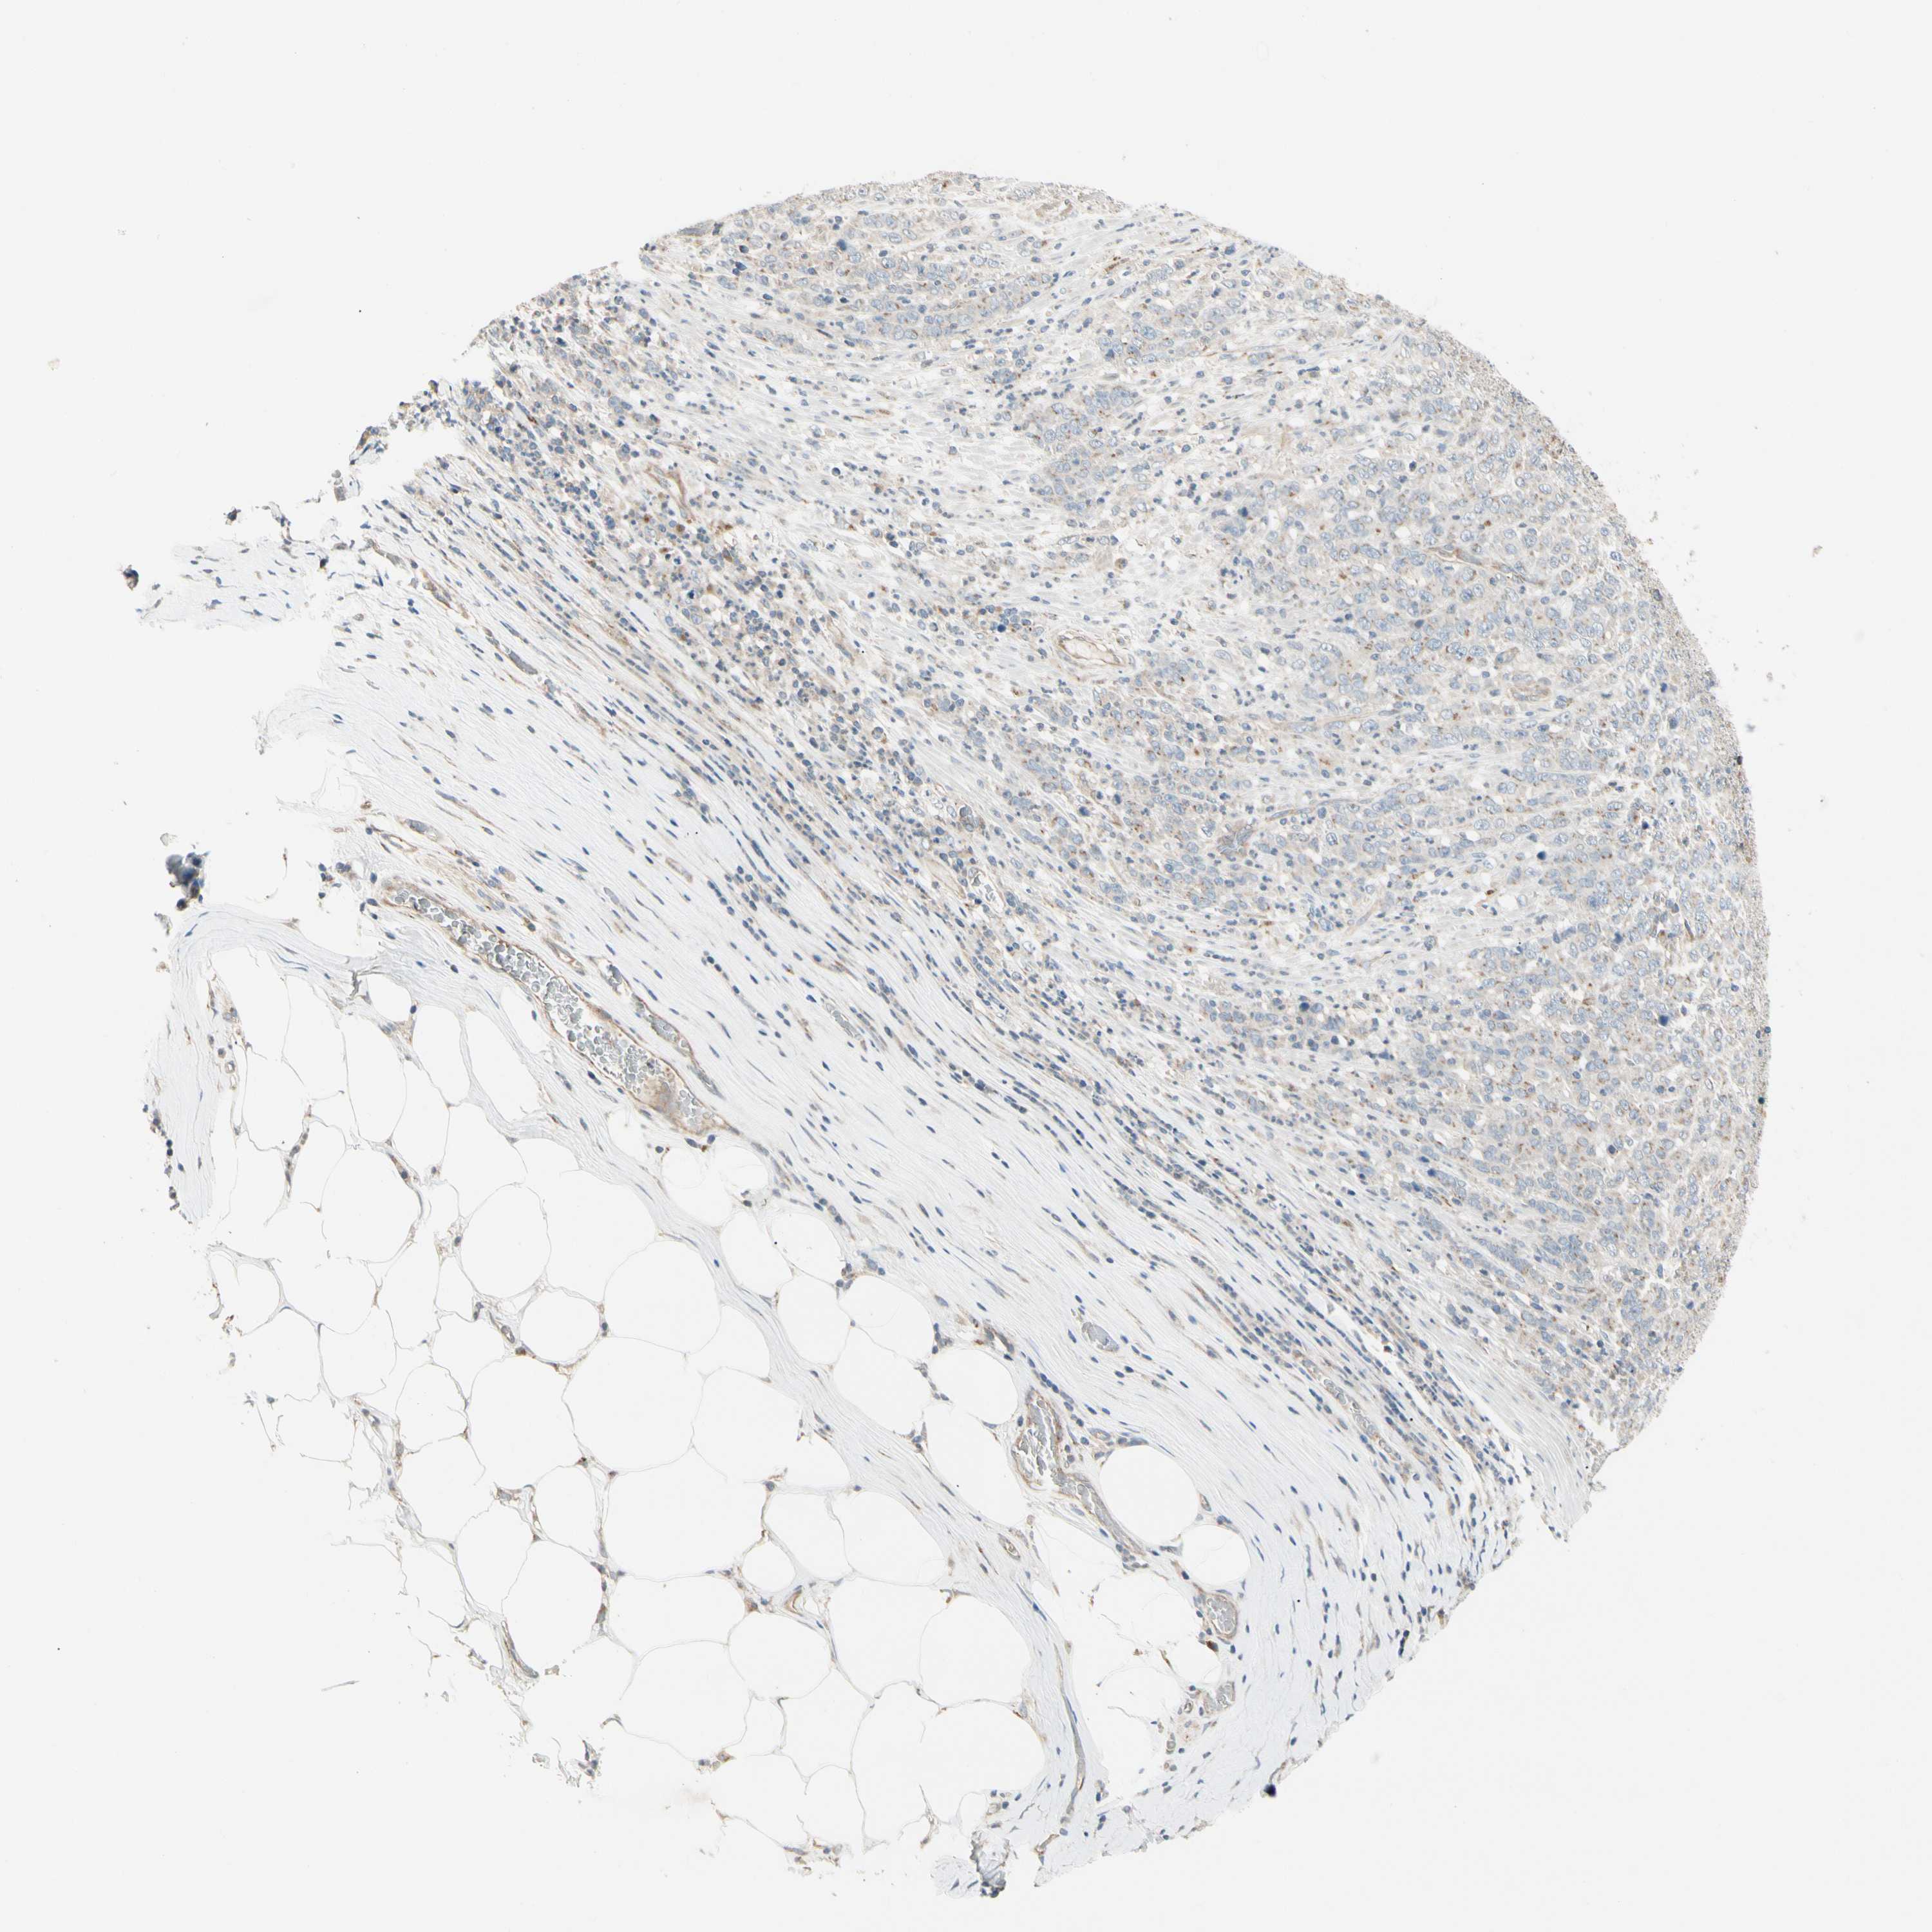

STOMACH CANCER - Protein expressioni

A mouse-over function shows sample information and annotation data. Click on an image to view it in a full screen mode. Samples can be filtered based on level of antibody staining by selecting one or several of the following categories: high, medium, low and not detected. The assay and annotation is described here.

Antibody stainingi

Antibody staining in the annotated cell types in the current human tissue is reported as not detected, low, medium, or high, based on conventional immunohistochemistry profiling in selected tissues. This score is based on the combination of the staining intensity and fraction of stained cells.

Each image is clickable and will lead to virtual microscopy that enables deeper exploration of all samples and also displays staining intensity scores, fraction scores and subcellular localization as well as patient and tissue information for each sample.

Antibody HPA007884

Staining

High

Medium

Low

Not detected

Intensity

Strong

Moderate

Weak

Negative

Quantity

>75%

75%-25%

<25%

None

Location

Nuclear

Cytoplasmic/membranous

Cytoplasmic/membranous,nuclear

Adenocarcinoma, NOS